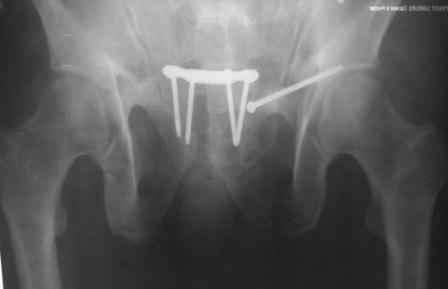

Отправитель: Ерсин 11 Апрель 2010, 21:18

X-ray!

x-ray.jpg

33KB (34105 bytes)

Отправитель: Ерсин 11 Апрель 2010, 21:19